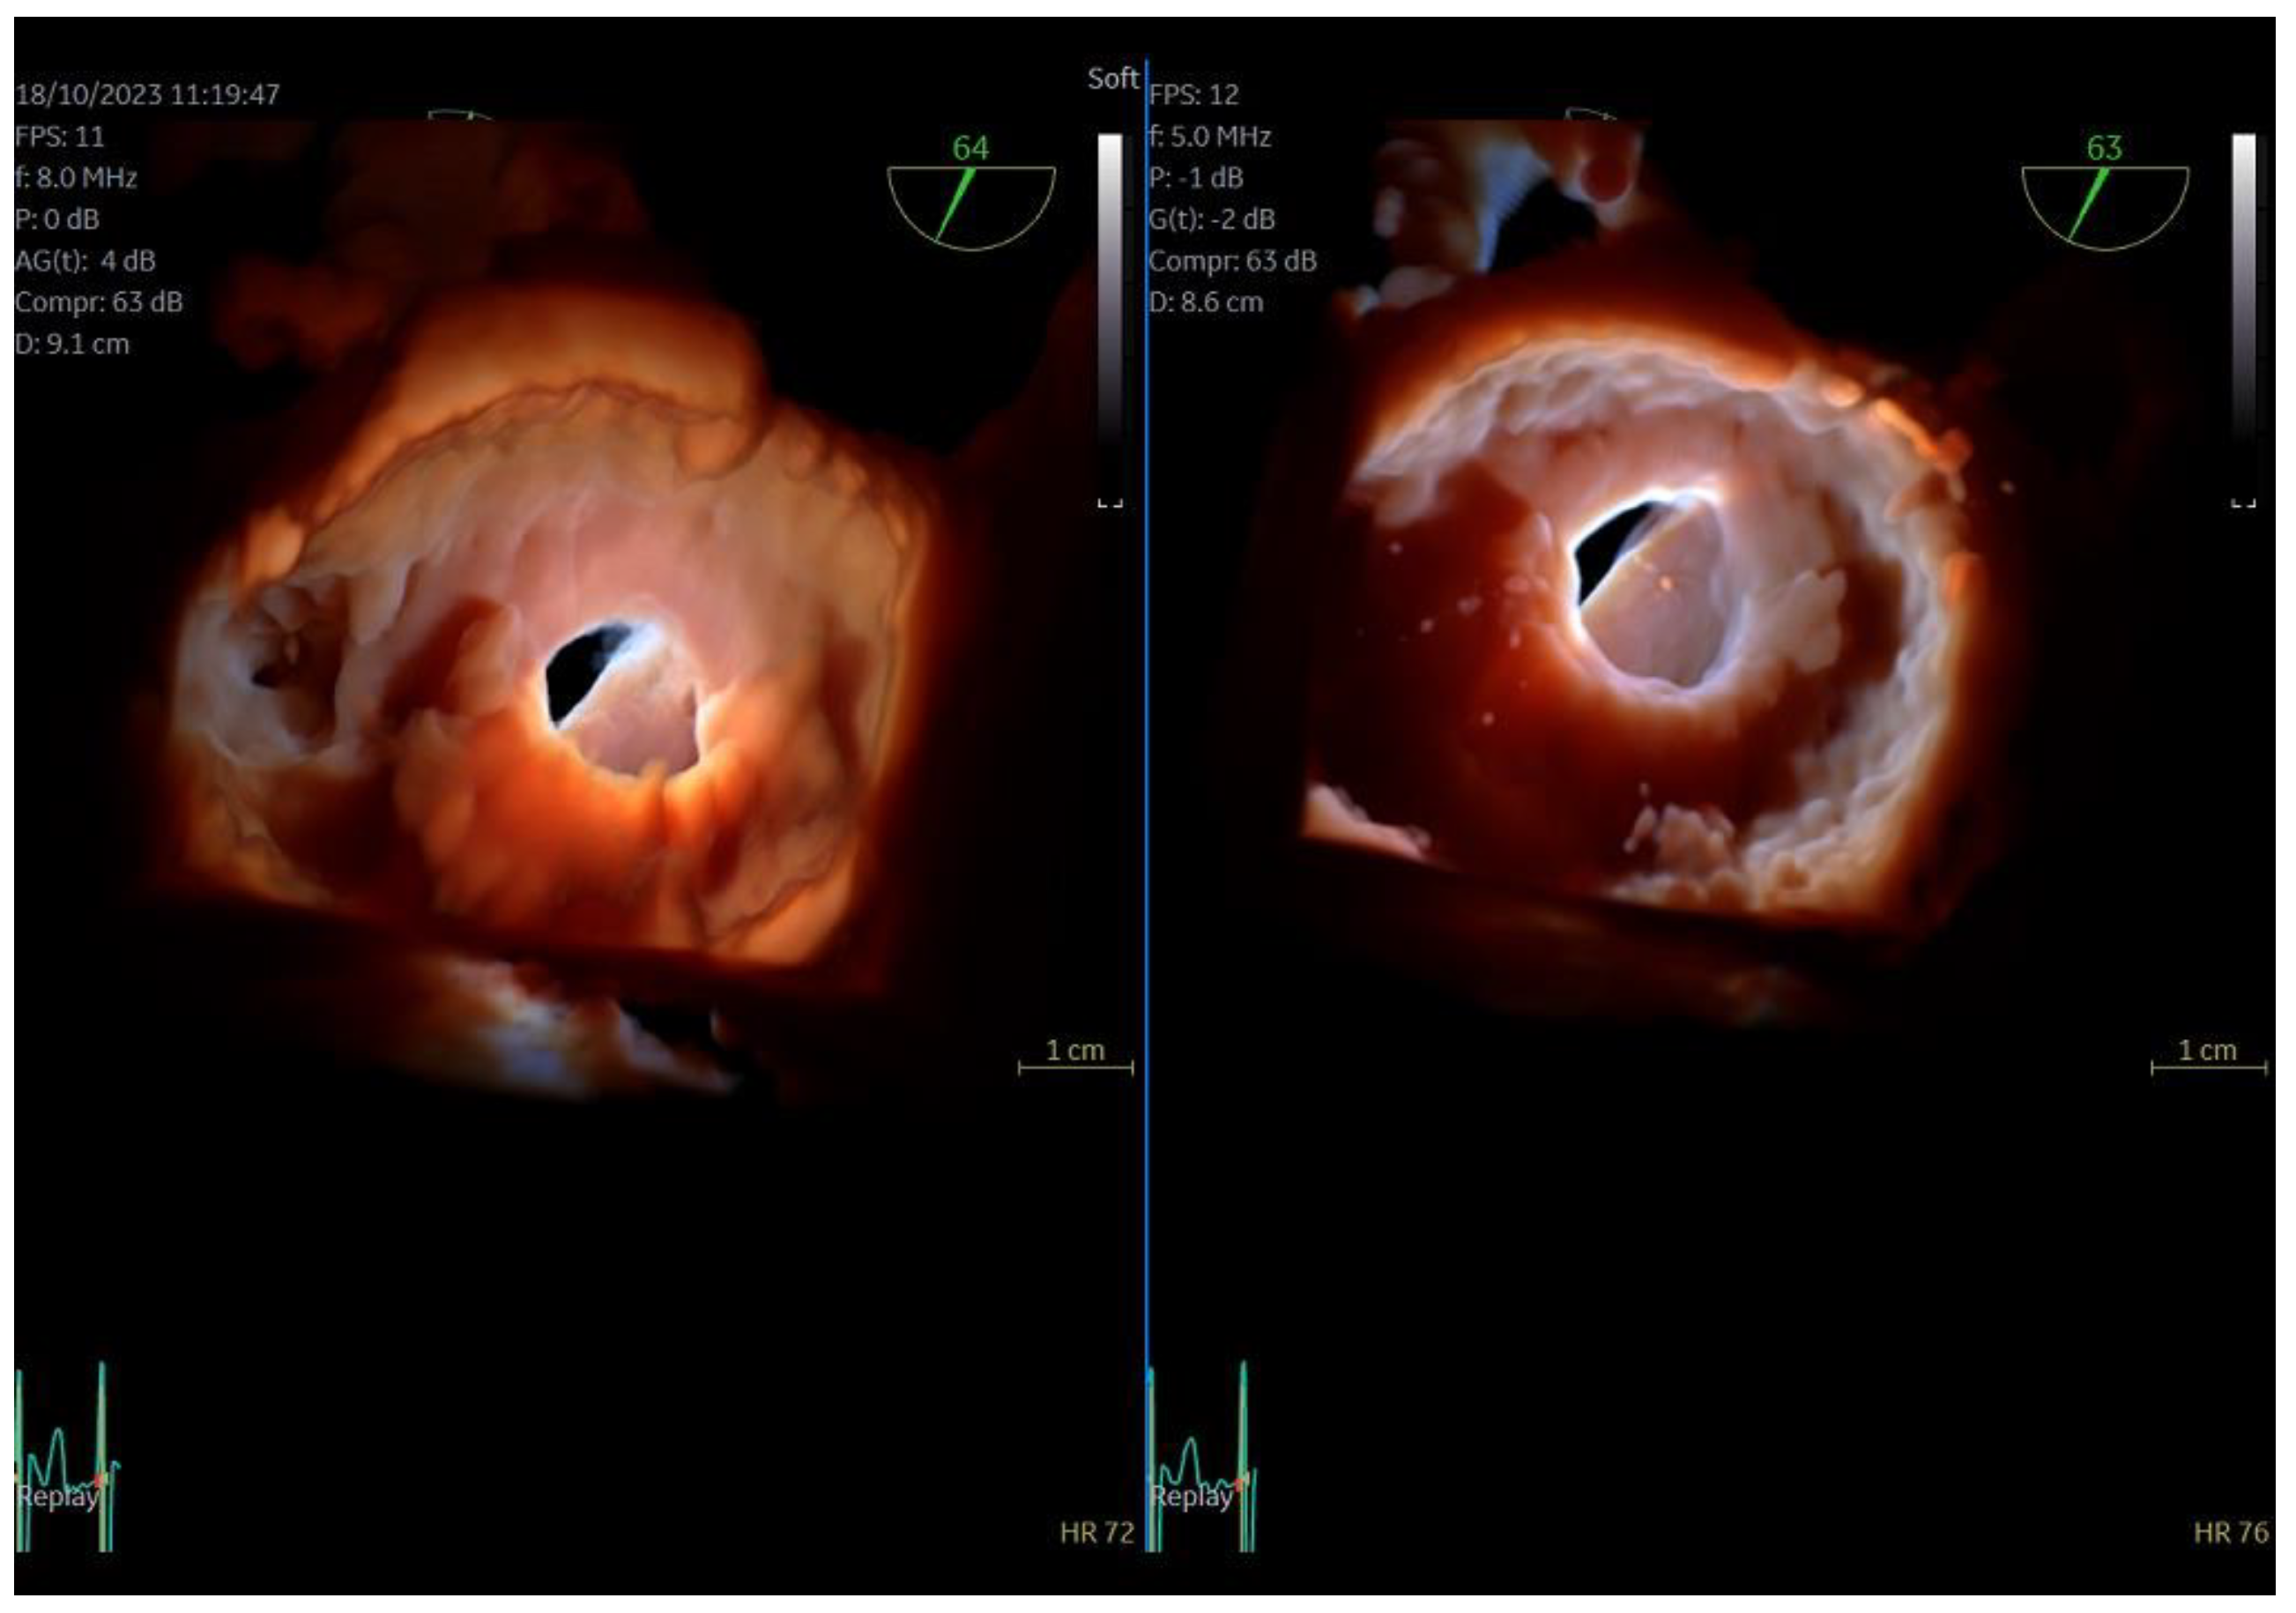

Figure 1.

Direct comparison of 3D volume −rendered “en face” images of a metallic prosthetic mitral valve with occluded disk. Left image corresponds to 6VT−D adult probe and right image corresponds to 9VT−D pediatric probe.

Figure 2.

Direct comparison of 3D volume-rendered “en face” images of a metallic prosthetic mitral valve with occluded disk. Left image corresponds to 6VT−D adult probe and right image corresponds to 9VT−D pediatric probe. Images enhanced with “photorealistic method” with Flexilight application (GE Healthcare).

The quality of images obtained with the 9VT-D pediatric probe and the accuracy of findings were assessed through examination of the first three patients. Each patient underwent a comprehensive TEE protocol using both the pediatric 9VT-D and adult 6VT-D probes, allowing for direct comparison of findings and image quality. Throughout the procedure, patients received local oropharyngeal lidocaine and mild sedation with midazolam to ensure tolerance.

The adult probe was initially inserted for complete 2D/4D image acquisition, followed by the insertion of the pediatric probe while the patient remained under sedation. Remarkably, insertion of the pediatric probe was effortless in all cases, requiring no additional sedation. Despite encountering challenging diagnostic scenarios in all three cases (1st patient: combined severe aortic stenosis and severe mitral regurgitation (MR) due to P1 scallop prolapse, 2nd patient: malfunction of metallic mitral valve prosthesis with an occluded disk, 3rd patient: bioprosthetic aortic valve with paravalvular leak and significant MR in previously MV repair with a complete ring), the pediatric probe consistently provided high-quality images comparable to those obtained with the standard adult probe (Figure 1 and Figure 2, video S4). Notably, there was no compromise in 2D and 4D spatial and temporal resolution, with only minor differences observed compared to the adult 6VT-D probe (Table 1). Evaluation using the 5-point scoring system consistently yielded an average score close to 5 for all three cases, indicating excellent image quality (Table 1).